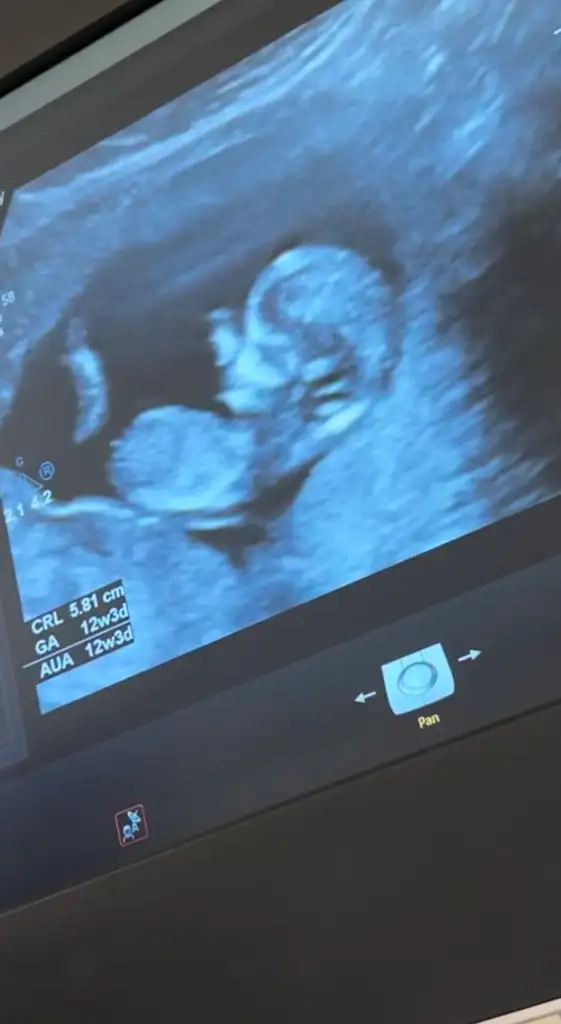

Lucky_16 Popüler Üye Kayıtlı Üye 3 Nisan 2019 1.306 533 123 39 9 Eylül 2025 Konu Sahibi Konu Sahibi Lucky_16 #1 kızlar hepinize merhaba 16 hafta bacak arası görüntüsü cinsiyet tahmini olan varmı Eklentiler IMG_2850.webp 11,1 KB · Görüntüleme: 165

A aslantub Yeni Üye Anneler Kulübü Kayıtlı Üye 10 Eylül 2025 31 1 1 28 10 Eylül 2025 Konu Sahibi Konu Sahibi Lucky_16 #7 Ay kızlar bana da bişey söyleyin lütfen meraktan çatlıyorum devletteki doktorlar 16haftadan önce yorum yapmıyor sizce cinsiyeti nedir Eklentiler IMG_3912.webp 17,6 KB · Görüntüleme: 130 IMG_3890.webp 40,7 KB · Görüntüleme: 150